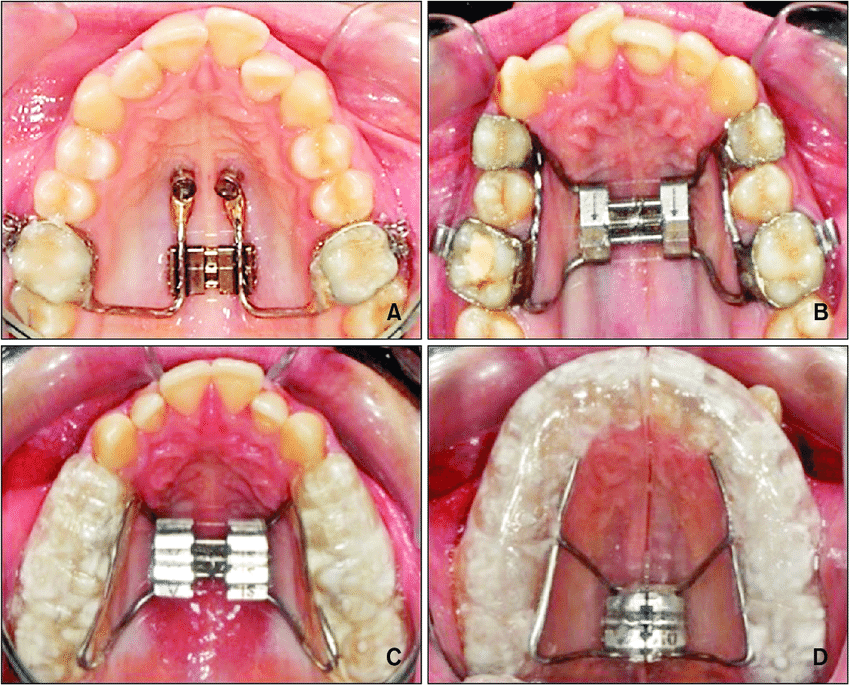

Atualmente, a ERM pode ser realizada em adultos por meio de duas principais abordagens:

- Expansão rápida assistida por mini-implantes (MARPE), que direciona as forças de expansão ao osso basal;

- Expansão rápida da maxila cirurgicamente assistida, indicada quando a resistência sutural inviabiliza a expansão ortopédica isolada.

A escolha da técnica deve considerar fatores como idade cronológica, maturação esquelética, espessura óssea palatina, padrão facial e objetivos do tratamento.

Dessa forma, a ERM deixou de ser exclusiva da ortodontia interceptiva e passou a integrar planejamentos mais complexos em adultos.

Os dispositivos mais utilizados incluem expansores do tipo Hyrax, Haas e suas variações contemporâneas, além de aparelhos assistidos por mini-implantes.

A instalação deve garantir estabilidade, adaptação passiva inicial e correta distribuição das forças.